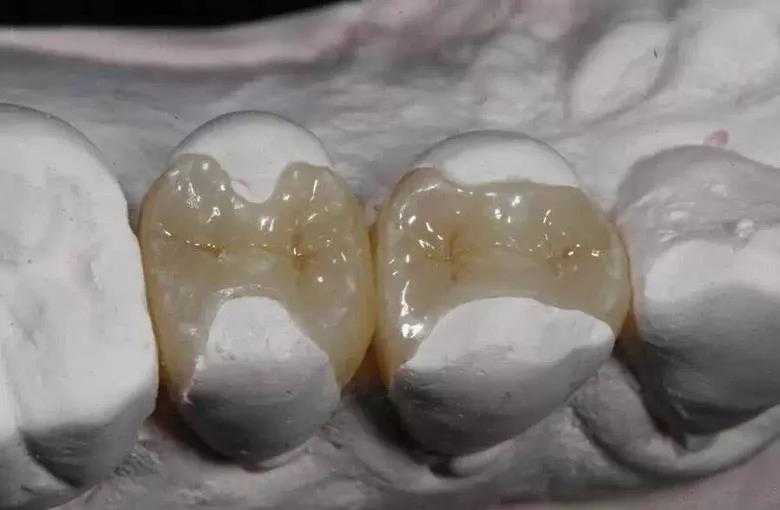

传统补牙做充填治疗时一般用银汞合金、光固化复合树脂等,不需要技工配合,医生可以独立完成,所需时间短、费用低。嵌体是在口外石膏模型上由专门的牙科技师制作出来的,然后再由临床医生将其戴入患者口内,最终粘固形成。

1、牙合面形态与对牙合牙高度协调。因为瓷嵌体是在模型上做的,可以360°全方位吻合牙缺损,高度效仿原牙的凹凸咬合关系,牙体预备量较少,能够保持牙齿外形的完整,减少牙髓牙周刺激,保留更多的牙体组织。

瓷嵌体:颜色逼真度高,但对医生的制作要求高,使用不当有碎裂可能,较金属嵌体导热性低,深龋不易刺激牙髓组织。